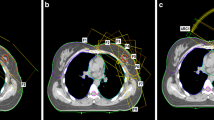

VMAT and IMRT plans

To acquire the necessary data for our study, we obtained computed tomography (CT) images of the upper body of the RANDO phantom (CIRS Inc., Norfolk, VA, USA), a widely-used anthropomorphic phantom for radiation dosimetry measurements, using a Discovery RT scanner (GE Healthcare, Waukesha, WI, USA) with a tube voltage of 120 kVp, tube current of 450 mA, and slice thickness of 2.5 mm. Treatment plans were then created using the Eclipse treatment planning system version 16.1 with the AAA dose calculation algorithm from Varian Medical Systems for both the TrueBeam and Halcyon linear accelerators (linac). Four plans were designed for Halcyon with FFF beam and for TrueBeam with FF beam: intensity-modulated radiation therapy with seven fields (7F-IMRT) and volumetric modulated arc therapy with two arcs (VMAT-2A), four arcs (VMAT-4A) and six arcs (VMAT-6A), as shown in Fig. 1. The prescribed dose for the entire left breast was set at 200 cGy for all plans (Table 1).